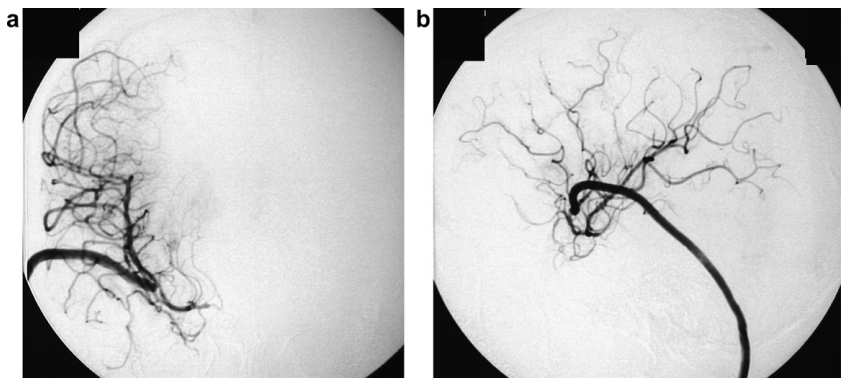

首次手术25天后影像复查发现动脉瘤在夹闭部位远端复发。医疗团队制定新的手术方案,采用高流量旁路术联合血管孤立术的治疗策略。

术后血管造影证实动脉瘤完全消失,新建血管旁路血流通畅。患者出现一过性偏瘫症状,一个月后神经功能基本完全恢复。